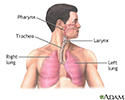

The flu (influenza) is a viral respiratory illness that causes fever, chills, runny nose, body aches, and cough. It spreads easily from person to person. The flu can cause moderate to severe symptoms. Most people recover fully. Children, older adults, and people with certain health conditions are at risk for severe illness and even death.

The flu is caused by an influenza virus.

Influenza - illustration

Influenza

illustration